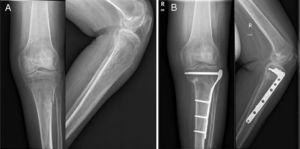

The fractures were divided into 2 groups, according to the therapeutic option for their treatment. The conservative group (C) comprised 12 fractures (4 femoral diaphyses, one femoral supracondylar, 2 proximal tibias, 2 tibial diaphyses and 3 tibial pylons) treated conservatively with plaster. The surgical group (Q) comprised 25 fractures treated surgically, because they presented displaced fractures (Figs. 1 and 2). The 25 fractures of group Q were 5 proximal femoral fractures, treated by intramedullary nail, 6 diaphyseal fractures stabilised by intramedullary nail (3 anterograde and 2 retrograde), 6 supracondylar fractures treated with retrograde intramedullary nail, 4 proximal tibial fractures treated with locking plates and screws, 3 diaphyseal tibial fractures synthesised by anterograde intramedullary nail (Fig. 3A), and one distal tibial stabilised by locking plates and screws (Fig. 3B).

Radiological results: the results were analysed using the criteria developed by Schmeiser et al.20 (Table 5). The radiological alignment data of both groups Q and C are described in Table 6 and Fig. 5A and B. With regard to healing, at the last radiological follow-up at 48 months, solid union of all the fractures was found in group Q, with a mean union at 14.5 weeks. In group C, at the last radiological follow-up, undertaken on average at 34.9 months, 4 of the 12 patients (33.3%)had no union and 2 had delayed union (21 weeks). The remainder of the fractures had good union, achieved at a mean of 15.9 weeks. A CAT scan was required between 3 and 6 months postoperatively in 83% of the patients. The statistical analysis found significant differences in favour of group Q (p<0.05) in terms of radiological union and radiological alignment.